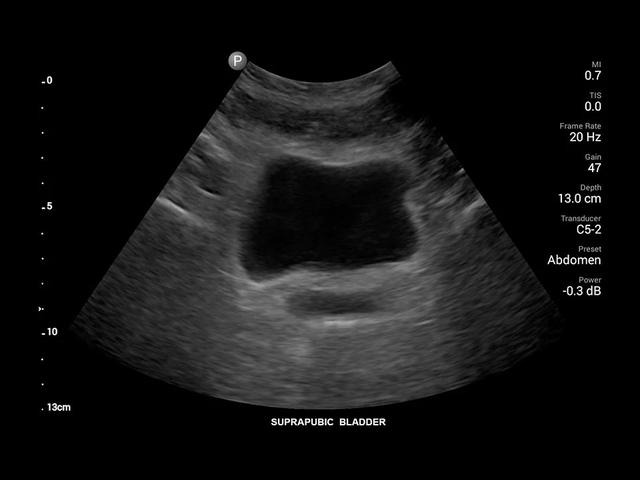

• Конвексный УЗИ датчик Philips C5-2